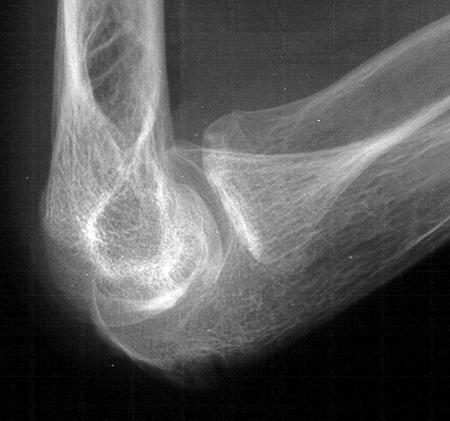

Plain films show humeral osteophytes and posttraumatic changes of the capitellum and radial head.